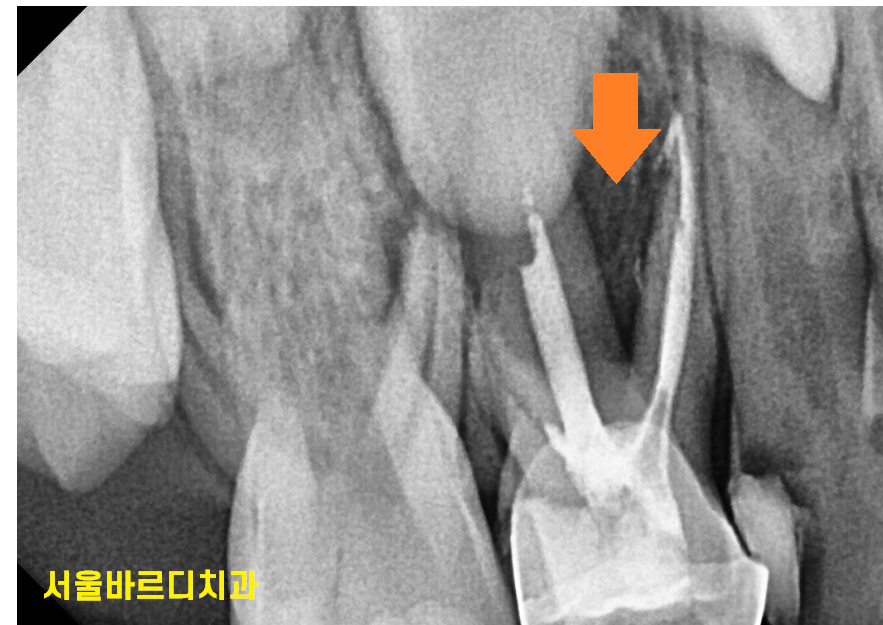

충치가 심해지면 뿌리 끝 염증이 생기고

잇몸에 뾰루지같은것도 올라올 수 있어요~

240802

문제는 유치 바로 밑에 영구치 씨앗이 위치한다는 것인데요.

영구치까지 염증이 퍼져 영향을 미칠 수 있다는 점이에요!

이렇게 되면 영구치가 올라와도 건강하지 않을 수 있답니다.

240809 염증이 심하여 유치 신경치료 후 은니를 씌워주었어요~!